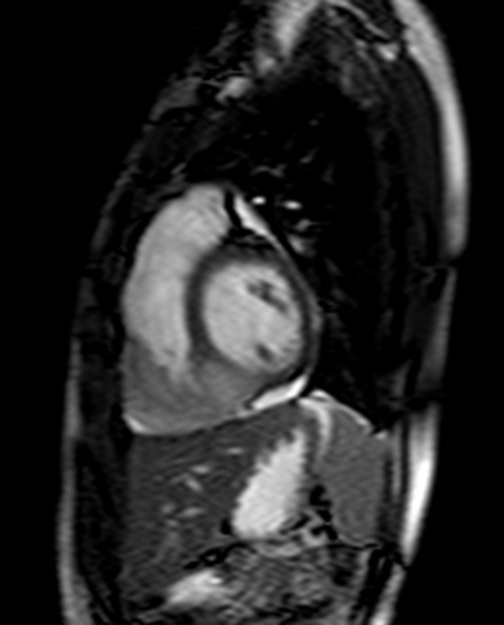

| 22yr / F, C.C. : Chest pain for 5 years, Anterior, mid-chest area, Aggravated by exercise, improved by resting, Dizziness (+), Palpitation (+) |